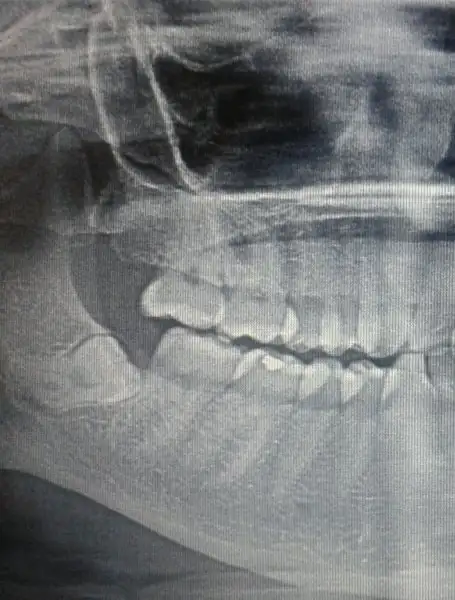

Üniversitede diş hekimliği fakültesinde çene cerrahına çektirdim hemde 4üde gömülüydü ameliyatla alındı.Yan yatmış durumdaydı biraz zor geçti. hayır ne uyuşukluk ne hissizlik nede çene çıkması yaşamadım.Korkmayın gözünüzü korkutmuşlar.Tekrar merhabalar bugun hastaneye gitmeden once ozele gittim fiyat ogrenmek icin rontgeni gosterdim inceleyip geldi altta olan 2 disin riskli dedi sinirlere yakin dedi isciligi var dedi. 800 tl istedi sadece 1 tanesi icin usttekiler bu kadar olmaz kolay cikacak gibi gorunuyor dedi. Bugun dis cerrahina gittim rontgeni gosterdim ve ozel doktorun soylediklerini tekrar ettim oyle bisey gorunmuyor dedi. Tek tek cekecegini soyledi yani 4 kere gitcem haftaya sali gunu gitcem birini cektirmek icin. Oradaki bayanlarla konustum 1 seneye kadar uyusukluk cene cikmasi falan olabiliyomus gozum korktu bi de ozeldeki sinire yakin riskli falan dedi acaba para kopartmak icin mi abartti yoksa gittigim doktormu biseyden anlamiyor anlamadim kafam karisti ins bi sorun cikmaz simdi baska biyerede gidemem randevuyu aldim kan tahlili yaptirdim bi de bebegimle gitmek cok zor oldu yorgunluktan oldum. Moralim bozuldu sende uyusukluk falan var mi hala devlet hastanesinde mi cektirmistin?

sinire yakın mı söylemedi doktorum bana ama kökü düzmüşGeçmiş olur inşallah

Senin diş sinire yakınmı

Benim diş te riskli ymiş.